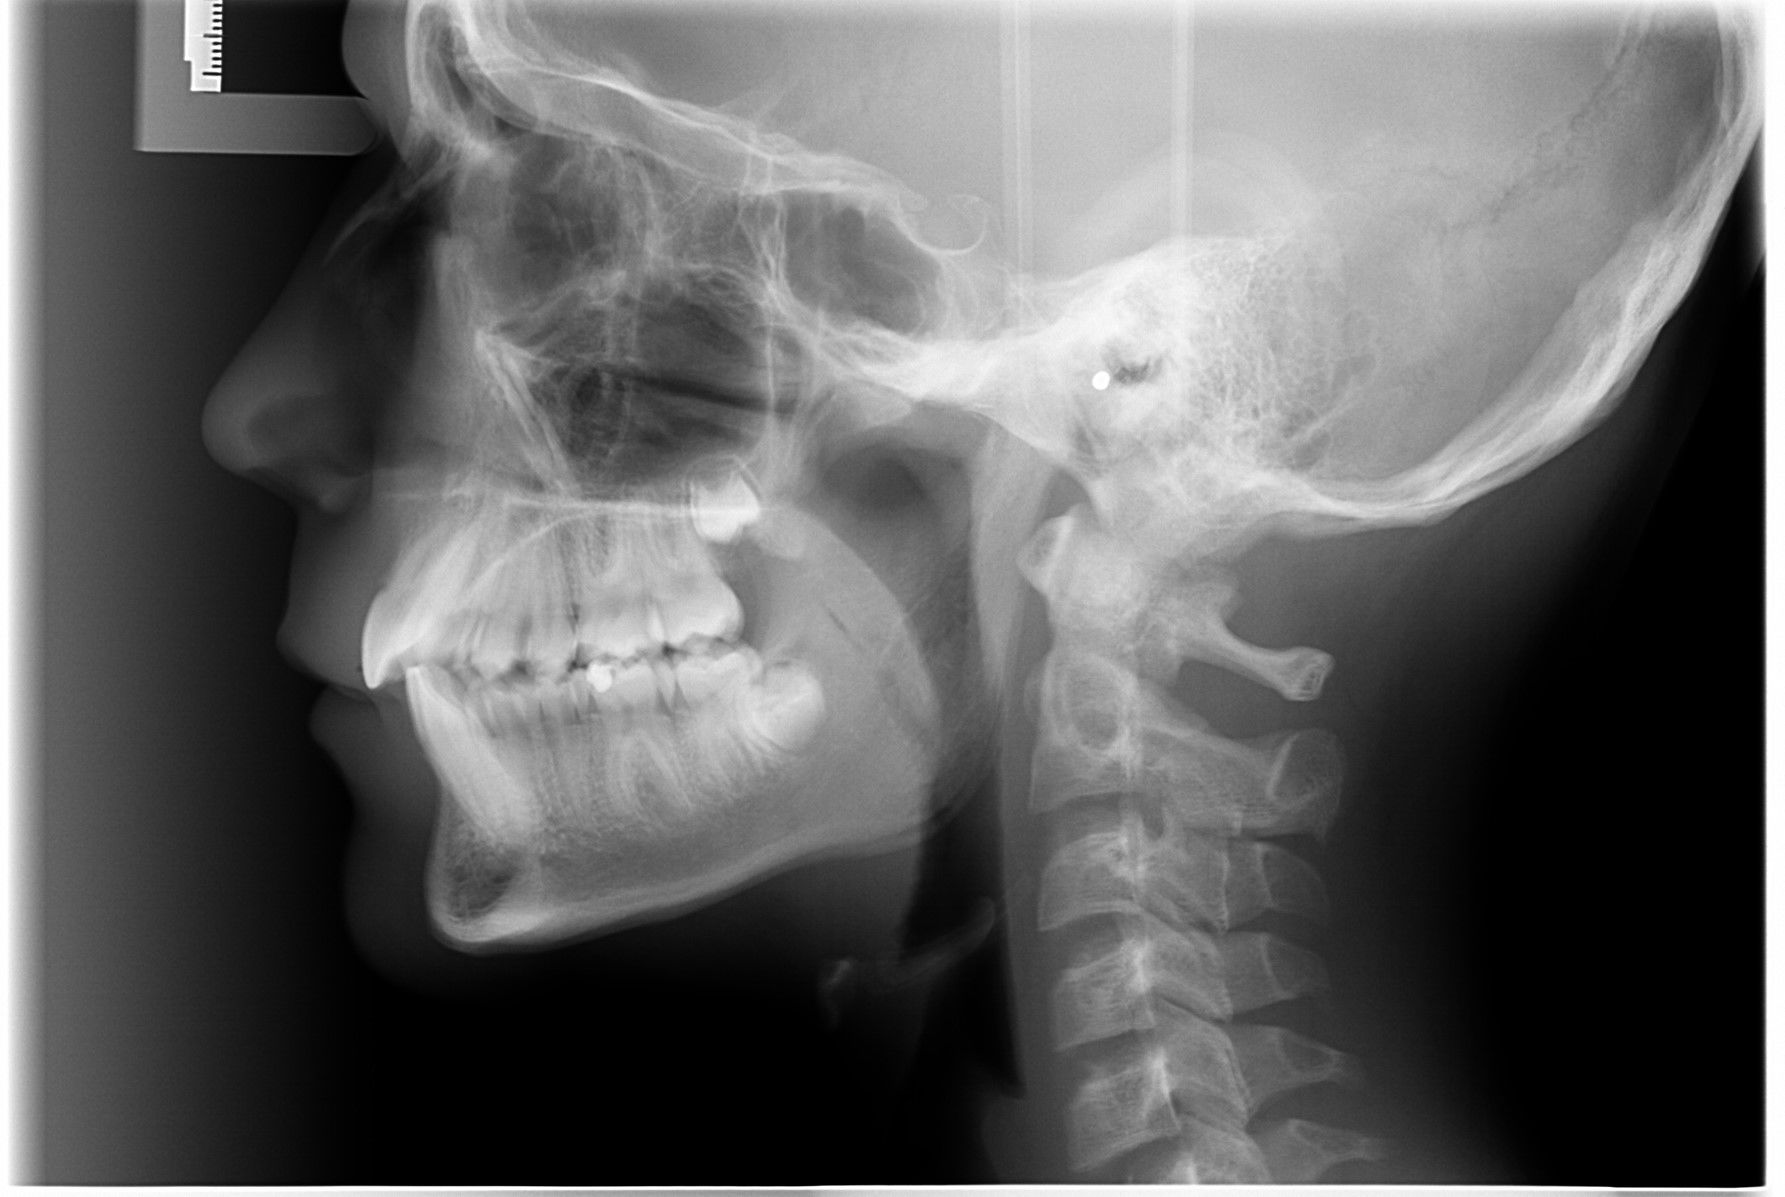

Vi tager røntgenbilleder af tænder, kæber og hoved.

Røntgen

Når du har takket ja til tandreguleringsbehandling, har du og dine forældre også givet accept til, at vi tager et røntgenbillede ca. hver 6. måned.

Vi tager røntgenbilleder for at kontrollere om rødderne kan klare belastningen med faste bøjler.